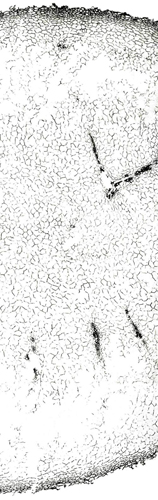

内部形態:鏡検

本品はほぼ偏球形を呈し、径1~2cmで、一端に茎の跡がある。外面は灰黄色~灰褐色で質は堅く、破砕面は黄色で平滑または灰黄緑色で粒状である。 本品はほとんどにおいがなく、味は苦い。 Corydalis属は、39節、約428種が広く世界に分布するといわれ、このうち38節,約288種が中国に分布している。このうち塊茎をつくるものは4節であり、分布が局地に限られるものを除くと、Sect. Duplotuberと Sect. Pes-gallinaceus の2つの節に限られる。Sect. Duplotuber にはチョウセンエンゴサク C. ternata (Nakai) Nakai (C. nakaii Ishidoya) および、ジロボウエンゴサク C. decumbens (Thunb.) Persが含まれる。Sect. Pesgallinaceusには C. yanhusuo Wang ex Su et Wu (C. turtschaninovii Besser forma yanhusuo Y. H. Chou et C. C. Hsu)が含まれるとされている。 |

内部形態の比較(市場品)

浙江省産市場品の横切面では、形成層は明瞭で環状につながっている。道管は形成層の近くに散在しており、中央に髄がある。コルク層を表面視するとコルク細胞は厚膜の長条形である。 韓国産市場品の横切面では、維管束が放射状に配列し、形成層は不明瞭で放射組織によって分断され、環状につながらない。コルク層を表面視すると、コルク細胞は薄膜の多角形である。

○延胡索 <韓国> |

兵庫県柏原における試験栽培品(浙江省産を種付け)は浙江省市場品と同様の形態を呈していた。 <横切面> ・形成層は明瞭で環状につながる。 ・道管は形成層の近くに散在している。 ・中央に髄がある。